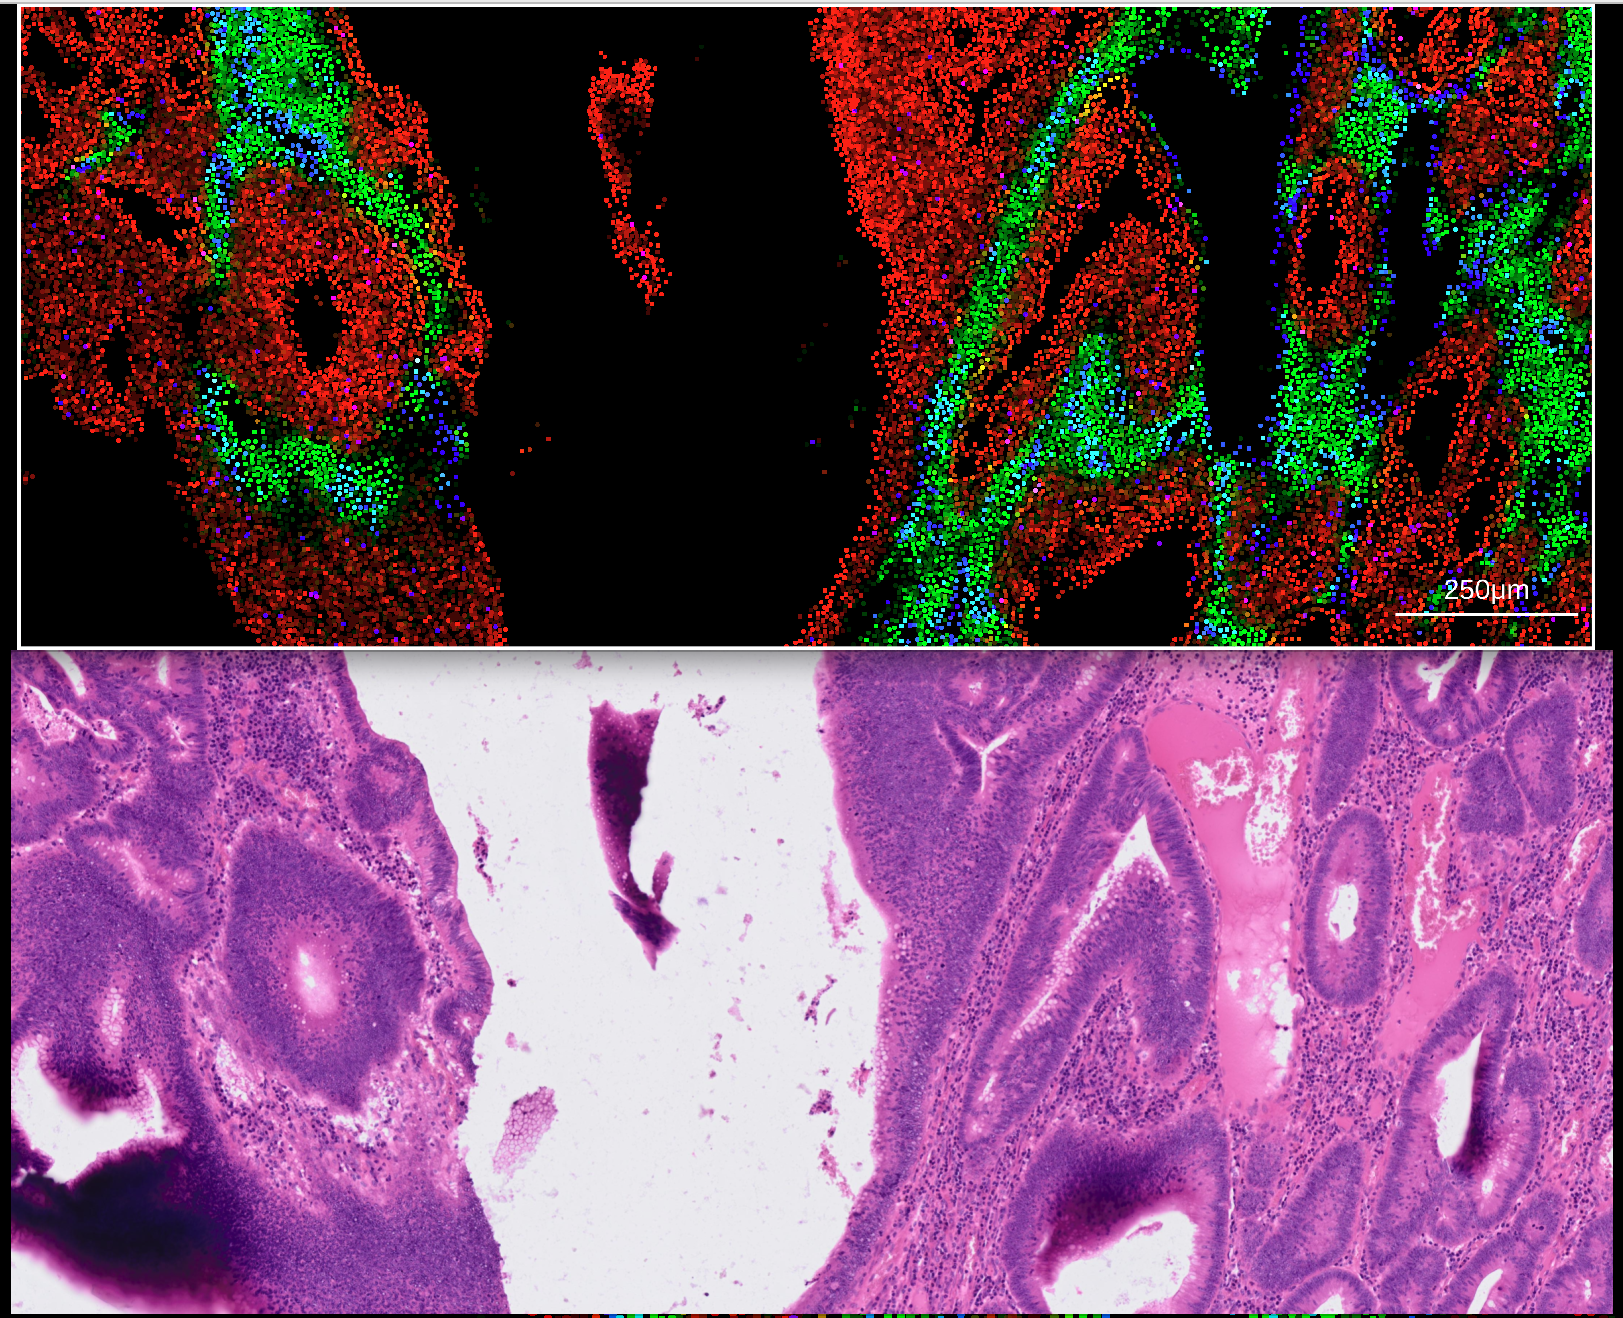

Large histopathlogy images such as H & E stains can be visualized in rakaia v0.23.0 and later alongside multiplexed image blends from both antibody-based assays and spatial assays. depending on the source of the multiplexed blend in the current session, rakaia may also be able to align the WSI coordinates to the current blend (currently this applies only to 10X assays such as Visium and Xenium).

To align the 10X Visium to its matched WSI, simply import a 10X Visium assay into the main canvas tab (see here for importing Visium data) and the corresponding WSI into the osd viewer. Once a Visium blend is made, simply zooming in on a subset of the spots in the main canvas will automatically transfer the coordinate bounds into the WSI view:

The transformation matrix should be exported in CSV format, and can then be imported into rakaia under File import -> Show/hide additional imports -> Choose or drop affine transformation matrix for WSI. Similar to 10X Visium, both the expression h5ad and WSI for the Xenium assay should be imported into the session. With the addition of the transformation matrix, zooming in on a Xenium canvas blend will trigger an update in the matched WSI: